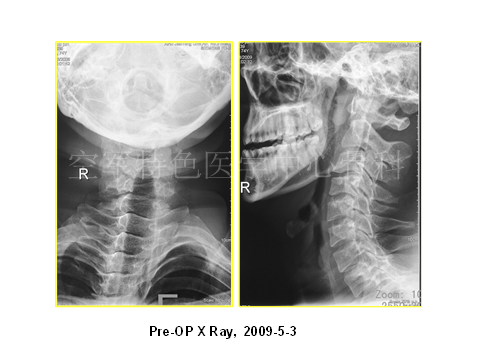

患者影像学资料如下:

介绍患者疾病情况后,陈宇飞医师邀请大家对进一步诊疗进行讨论:(1)患者目前的主要诊断是什么,颈椎间盘突出症?颈椎管狭窄症?脑瘫后遗症?脊髓亚急性联合变性?(2)治疗方案如何选择,是保守治疗,还是手术治疗,手术方案是什么?